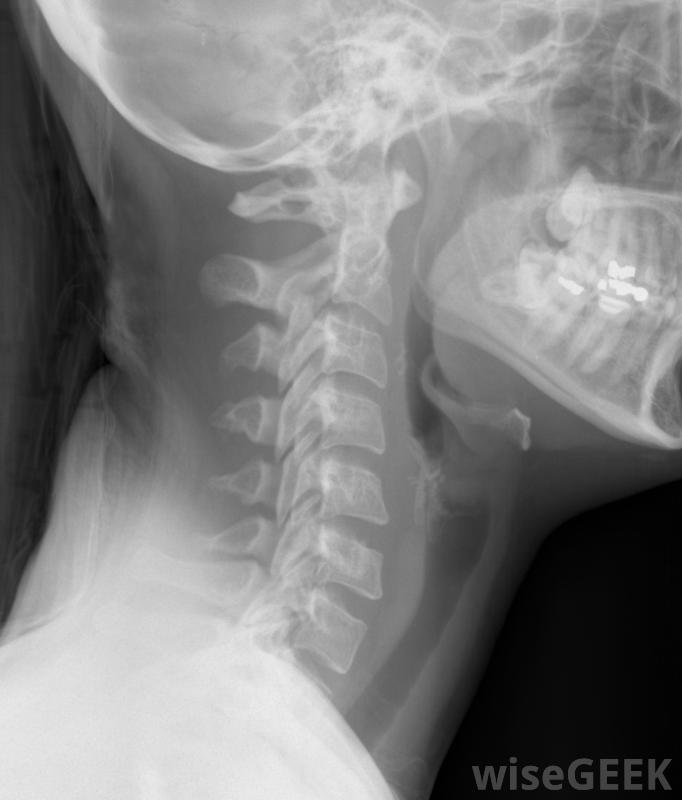

颈椎由七根脊椎组成,支撑着大脑和头骨。它保护着身体上部的各种神经,如脸、颈、喉、臂和手。颈领,也称为颈托或颈托,用于支撑头部和脊髓的颈部。它限制颈部和脊椎的运动,使损伤得以愈合,并有助于防止损伤的发生。颈部X光片,包括颈椎。颈托通常用于紧急情况下和短期治疗。当头部或颈部受伤时,脊髓损伤的危险是一个值得关注的问题。在紧急情况下,颈环通常被放置在适当的位置上,以防止这种情况的发生。颈环有时也用于治疗颈部疼痛,如颈部扭伤,并使脊髓重新排列戴颈领的妇女。有四种基本类型的颈领:软泡沫、凝胶填充的热敷或冷敷、泡沫固定和胸骨枕下颌骨固定器(SOMI)的一种支架。它可以牢固地固定在颈部和上身,通常用尼龙搭扣或其他简单的带子固定。它们有各种尺寸,一般很容易清洗。颈托通常被制作成随时佩戴,包括在睡觉时事故发生后,有时建议使用颈部项圈来治疗严重的颈部扭伤。软泡沫项圈可帮助减轻颈部轻微损伤引起的肌肉紧张或疼痛。这是最常见的一种颈领,也是最经济的一种。软泡沫项圈只适合颈部,所以颈部活动范围有限。对于颈部轻微损伤,如僵硬或炎症,通常使用凝胶填充的热敷或冷敷领口。类似于软泡沫领,这种领子里的包是冷冻或加热的,放在针织或尼龙袖子里,固定在脖子上。这些类型的领子比一般的加热垫和冰袋要省事泡沫固定项圈,也称为费城颈部项圈,通常用于在软组织损伤后帮助加强颈部,比如颈部扭伤或颈部扭伤。致密的泡沫塑料项圈位于肩膀上部,颈部高度可调,使下巴能够舒适地休息,大多数都有气管切开的开口。通常在上身安装一个索米支架来限制头部、颈部、关节和脊柱的运动。这种类型的项圈通常用于治疗颈椎骨折,脊髓损伤和严重的头颈部创伤它通常是在医院里穿的,而且通常在任何时候都穿着,即使是在洗澡或穿衣的时候,黑色或棕褐色。药店或零售店通常出售软泡沫或凝胶填充的颈环。其他颈环通常需要医生处方,因为它们是为每个人量身定制的。颈领可用于治疗颈部疼痛或重新排列脊髓。